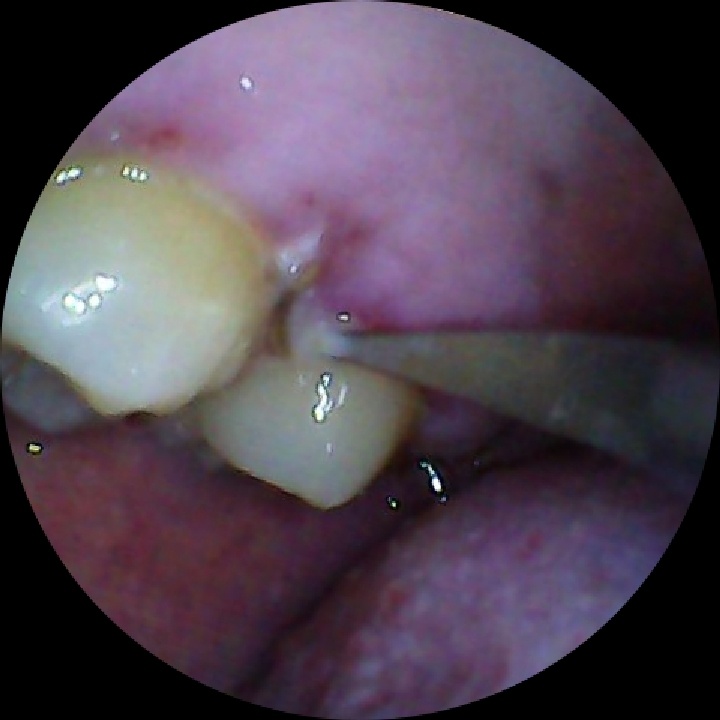

刷牙莫名其妙掉了一块牙结石。之后刷牙就有点出血。自己检查了一下,发现有点充血点,

刷牙莫名其妙掉了一块牙结石。之后刷牙就有点出血。

自己检查了一下,发现有点充血点,根本又刮出来一块牙结石。

可能跟之前用抗牙结石牙膏有关,不然应该是不会自己掉下来的。

看来要洗牙了还没洗过,先消炎几天再去。